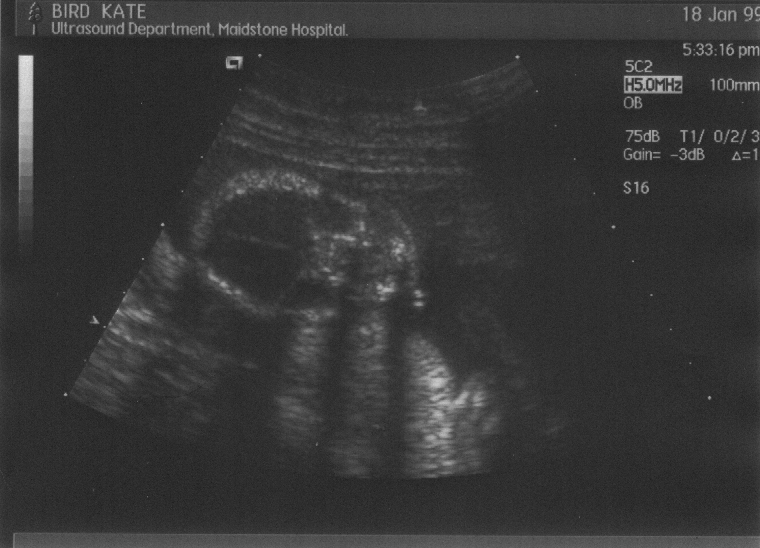

These are the six scans taken at the week–20 “abnormality scan”. Click on the thumbnail to view the full picture :-

Week 20, scan 1  (bust, side–on)